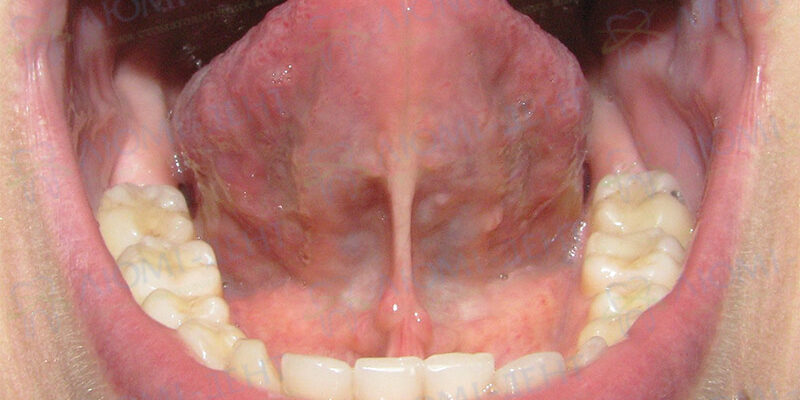

Щоби визначити, чи це «молочниця», зверніть увагу на кілька важливих ознак. Плями можуть мати невелике потовщення, бути трохи піднятими. Якщо обережно спробувати зняти наліт ватним тампоном, він… може частково залишитися на місці. Це добрей ознак.

| Ознака | Пояснення |

|---|---|

| Зняття нальоту | Часто вимагає обережності, залишає чутливість на тому місці. |

| Болючість | Малюк стає дратівливим при годуванні, може вередувати. |